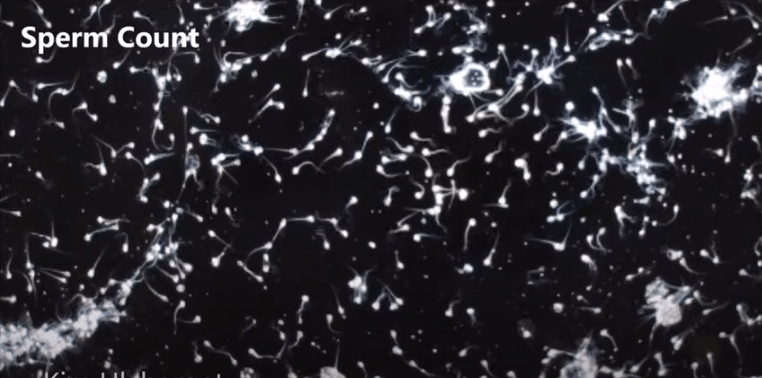

Wie die Epidemiologin in ihrem neuen Buch „Countdown“ erörtert, enthielt das männliche Ejakulat im Jahr 1973 ca. 99 Millionen Spermien pro Millimeter. 38 Jahre später 2011 belief sich die Spermienzahl nur noch auf 47 Millionen pro Millimeter. Sollte sich dieser Trend unbeeinträchtigt in diesem Ausmaß fortsetzen, hieße das rein rechnerisch, dass die Spermienzahl im Jahr 2045 die Nullmarke erreichte. Zero! Mit anderen Worten keine Fortpflanzung mehr. Keine Babys. Keine Menschen. Dies muss man erstmal sacken lassen.

Swan zufolge seien neben Stress vor allem die bereits oben erwähnten Endokrinen Disruptoren verantwortlich, für das globale Spermien-Sterben. Dabei handelt es sich um allgegenwärtige Chemikalien in unserer Umwelt. Diese befinden sich in Nahrungsmittelverpackungen, Kosmetika-Produkten, in Plastik, Elektrogeräten, Shampoos, Parfüms, Reinigungsmitteln, wasserfesten Kleidungsstücken, Teppichen etc..

Zu den Spermien-Killern gehören auch sogenannte Phthalate (Weichmacher). Substantielle Chemikalien in Plastik, die mitunter für die Abnahme der Testosteronkonzentration im Körper sorgen. Wie Dr. Swan dem wissenschaftlichen Portal „Future Human“ mitteilte, habe sie der Erforschung von Phtalaten und deren Auswirkungen am meisten Aufmerksamkeit gewidmet. Nach ihr stellten Weichmacher die größte Gefahr für die männliche Fertilität dar. Insbesondere weil die hochgradigste Kontamination über die Nahrungsmittelzufuhr stattfinde.

Denn die Endokrinen Disruptoren gelangten in den Mutterleib und anschließend zu den Hoden des Fötus. Wodurch eine markante Entwicklungsveränderung hervorgerufen würde. Sobald das Kind alt genug ist um Spermien zu entwickeln, ist es bereits steril. Sprich die Spermienzahl ist unzureichend, um Eizellen zu befruchten.